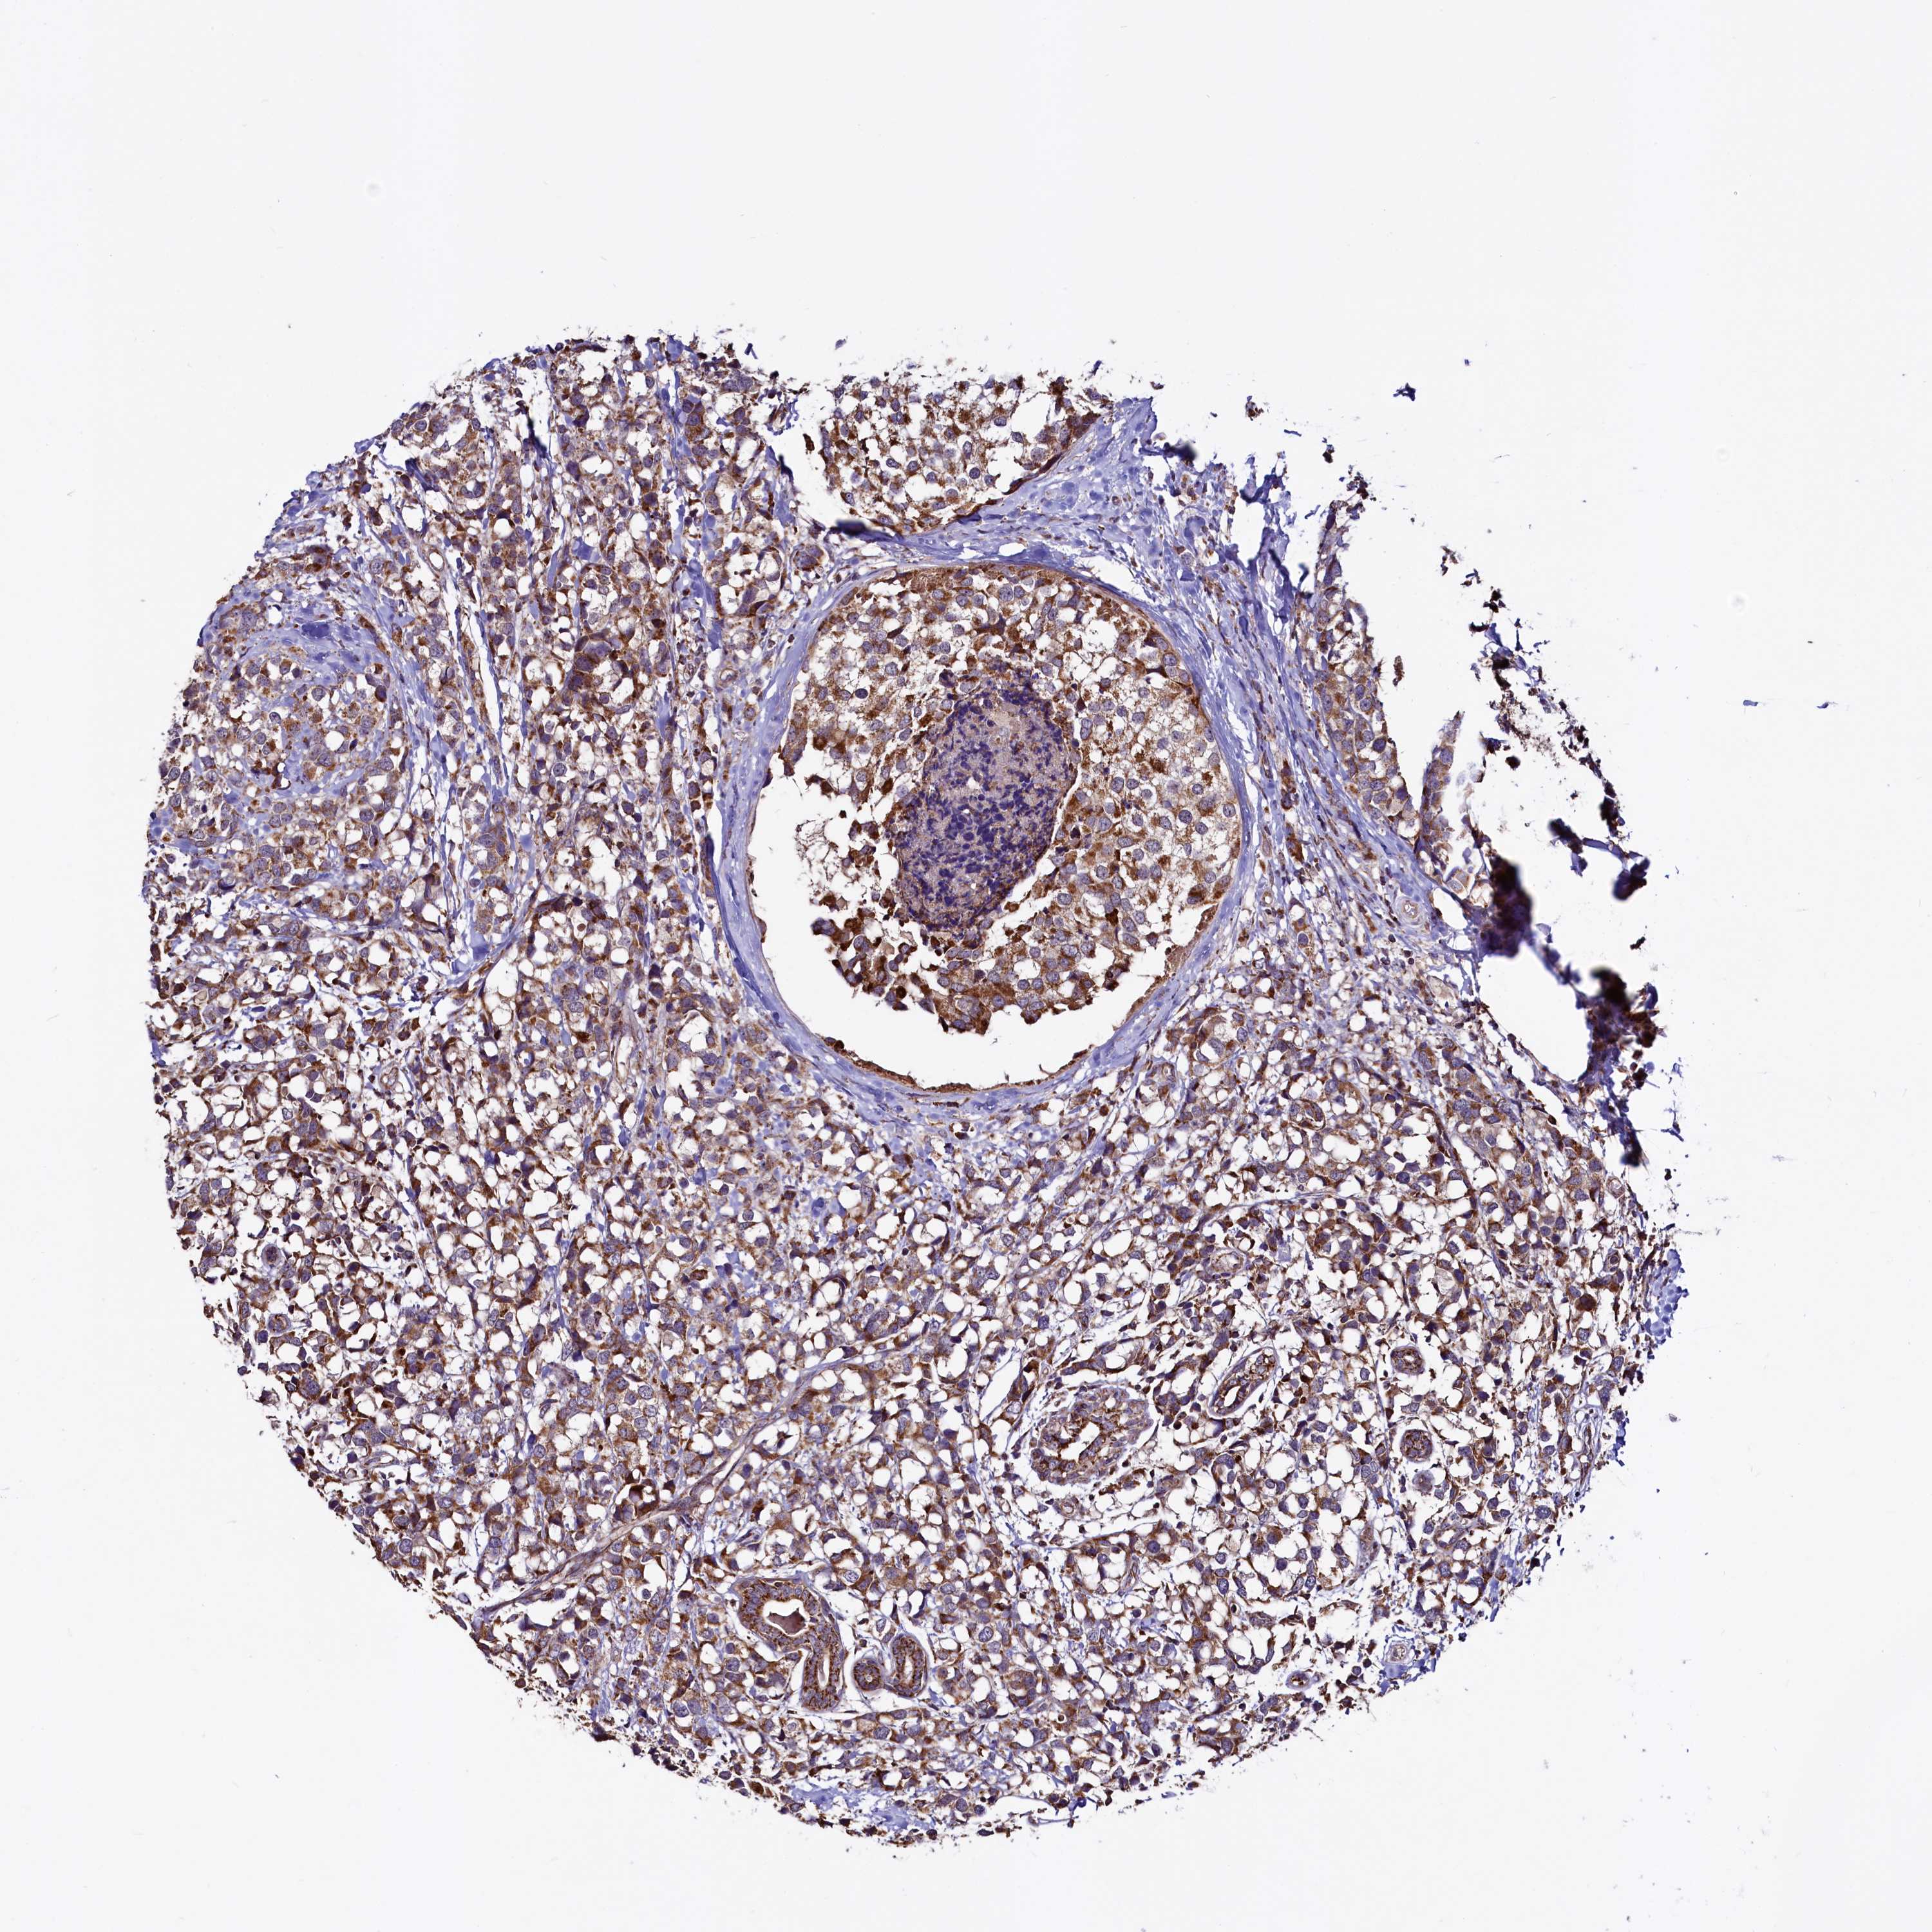

BRCA TCGA BRCA VALIDATION PROTEIN EXPRESSION